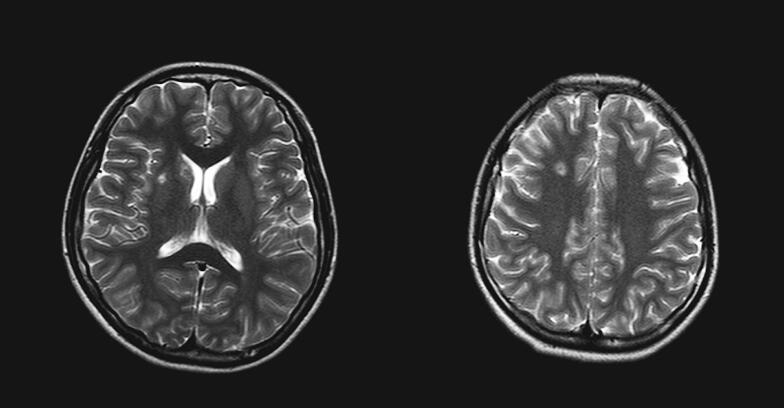

入院第5天患者诉头痛,查体颈部有抵抗,行头颅MRI(图1)示右侧额、顶叶白质区和右基底节区、左侧小脑内多发性病变,颅内感染性病变合并脑膜炎。

图1入院第5日行头颅MRI示右侧额、顶叶白质区和右基底节区、左侧小脑内多发性病变,颅内感染性病变合并脑膜炎

入院第6天血培养回报:金黄色葡萄球菌,对万古霉素敏感,遂改为盐酸万古霉素(2.0g/d)联合硫酸异帕米星(400mg/d)抗感染,此后体温逐渐降至正常范围。复查血常规、cTnI恢复正常。复查心脏彩超示二尖瓣后叶部分腱索断裂伴反流(++++),赘生物消失。颅脑MRI(图2)示右侧额叶、左侧小脑半球病变基本吸收,右侧顶叶病变明显吸收,右侧豆状核病变有所吸收,脑膜强化程度有所减轻。入院第39天患者出院并前往其他医院进行心脏手术。

图2 入院第18日复查颅脑MRI示右侧额叶、左侧小脑半球病变基本吸收,右侧顶叶病变明显吸收,右侧豆状核病变有所吸收,脑膜强化程度有所减轻